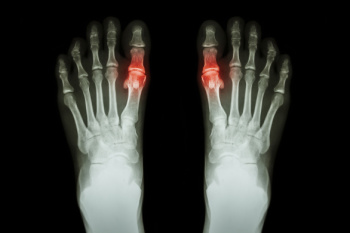

Gout in Teenagers

Gout is a crystalline inflammatory arthritis caused by the buildup of uric acid crystals within the joints. Although it is more common in adults, the prevalence of gout among teenagers is increasing due to obesity, poor diet, and certain medical conditions. It often affects the big toe, causing sudden joint pain, redness, swelling, and warmth. Repeated flare-ups may lead to joint deformities and, in severe cases, may contribute to kidney dysfunction and other systemic concerns. Risk factors include family history, metabolic disorders, and high consumption of sugary beverages or processed foods. A podiatrist can diagnose gout, manage painful symptoms, and coordinate comprehensive care. If your teenager has symptoms of gout, it is suggested that you consult a podiatrist who can provide an accurate diagnosis and relief options.

Gout is a form of arthritis that is characterized by sudden, severe attacks of pain, redness, and tenderness in the joints. The condition usually affects the joint at the base of the big toe. A gout attack can occur at any random time, such as the middle of the night while you are asleep.

Symptoms of gout are warmth, swelling, discoloration, and tenderness in the affected joint area. The small joint on the big toe is the most common place for a gout attack to occur.